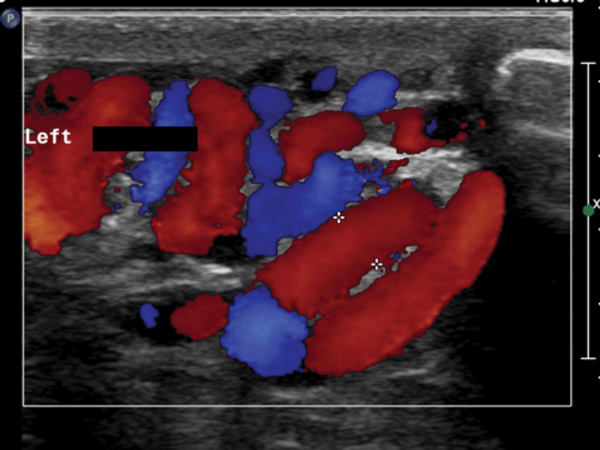

- What does this Doppler ultrasound image show?

Left sided varicocoele.

- What is the investigation of choice to diagnose a varicocoele?

Colour doppler ultrasound study.